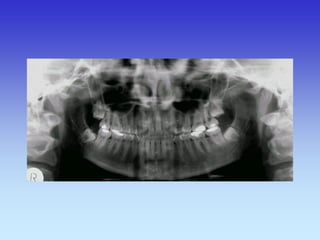

KOSTI GLAVE

Kosti lubanje – rtg.